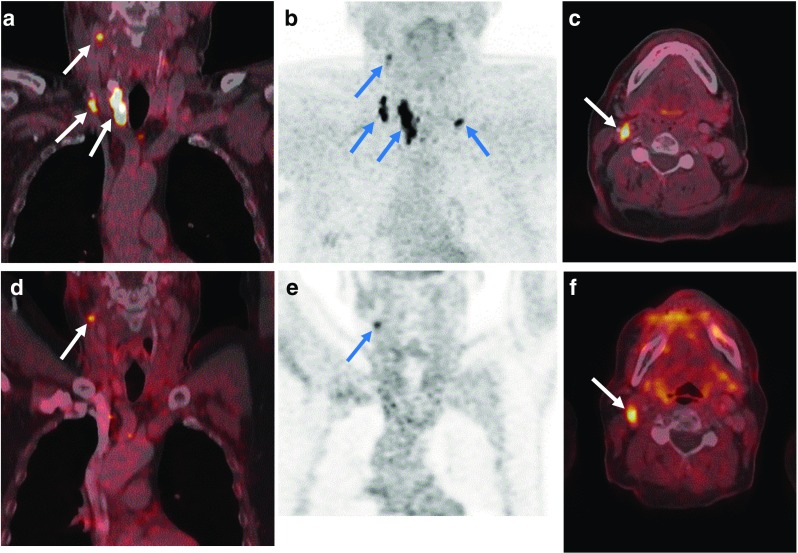

Two months after surgery, 14 patients showed measurable bCtn levels and were categorized as having persistent MTC, while 17 patients showed no detectable levels of bCtn and sCtn. The median (range) postoperative bCtn, sCtn and CEA levels were 0.5 pg/ml (0–23,647 pg/ml), 0.5 pg/ml (0–244,000 pg/ml) and 2.6 μg/ml (0–1,426 μg/ml), respectively. LN with increased DOPA decarboxylase activity were detected on follow-up [18F]DOPA PET/CT examinations in these patients ([18F]DOPA PET/CT imaging in representative patients is shown in Figs. 3, 4, 5, and 6). The patient with the highest Ctn levels showed liver metastases on the first follow-up scan 2 months after surgery.

Fig. 4.

A 61-year-old male patient with persistently elevated basal calcitonin levels postoperatively. a–c Preoperative [18F]DOPA PET/CT images show increased DOPA uptake in the primary tumour in the right thyroid lobe as well as multiple bilateral DOPA-positive cervical lymph nodes (levels II, III, IV and VI). d–f Postoperative [18F]DOPA PET/CT images in the same patient 2 months after total thyroidectomy with central and bilateral neck dissection, show a residual lymph node with focal DOPA uptake in the right upper cervical region (level II)

Fig. 5.

A 47-year-old female patient with further increasing basal calcitonin levels after surgery. a–c Preoperative [18F]DOPA PET/CT images show a DOPA-positive primary tumour in the right thyroid lobe with multiple DOPA-positive lymph nodes in the right cervical region (levels II, III, IV and V) as well as in the lower central region (level VI). d–f Postoperative [18F]DOPA PET/CT images in the same patient show persistently DOPA-positive lymph nodes in the right upper accessory level V and central level VI

Fig. 6.

A 65-year-old female patient with MTC and bilateral lymph node metastases with persistently elevated levels of serum basal calcitonin after surgery. a, b Preoperative [18F]DOPA PET/CT images show DOPA-positive primary tumour in the right thyroid lobe with bilateral DOPA-positive lymph nodes in the cervical region (levels II, III and IV) and central region (level VI). c, d [18F]DOPA PET/CT images in the same patient 2 months after total thyroidectomy, and central and bilateral lymph node dissection, show a DOPA-positive residual lymph node in the upper right cervical region (level II)

As surgery is the only method with curative intent in MTC [4], preoperative risk stratification might be almost as important as accurate staging. We found that the preoperative cN1b status on [18F]DOPA PET/CT, the number of involved LN regions and the preoperative levels of both bCtn and CEA are predictive of postoperative tumour persistence and recurrence. This has also been demonstrated in a larger cohort for bCtn with a comparable cut-off value of >1,000 pg/ml [21]. However, although our cohort was comparatively small for an outcome prediction analysis, DOPA PET/CT cN1b status was the only independent predictor of postoperative tumour persistence/recurrence in the multivariate analysis. The results suggest that [18F]DOPA PET/CT provides superior preoperative outcome prediction to the known tumour markers while additionally providing information about the respective LN locations. Nevertheless, in comparison to the postoperative [18F]DOPA PET/CT examinations (Figs. 3, 4, 5 and 6), postoperative persistence of MTC was mainly detected in cervical LNs already known from preoperative imaging. Reasonable explanations for this finding could be either that the small size of the involved LNs hampered the intraoperative detection process or that surgical nontargeted exploration of the involved LN level would have caused an unreasonable risk of sever side effects. Both issues might be addressed in the future using the higher detection rate of [18F]DOPA in a radioguided surgical approach which might allow rapid intraoperative detection of the involved LNs and therefore reduce the rate of MTC persistence. As this method has already been implemented in other surgical/oncological fields and has demonstrated very promising outcomes [22], the low physiological background of [18F]DOPA in the head and neck region could enable the detection of small MTC lesions with an intraoperative gamma probe.